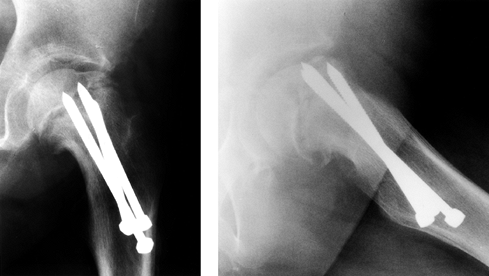

Figure 172.3.

Preoperative planning for the Southwick intertrochanteric osteotomy. AP

and frog-pelvis radiographs of a 14-year-old boy with a left SCFE. A:

The epiphyseal–shaft angle on the AP view is 150° on the normal side

and 125° on the affected side; thus a 25° wedge is needed. B:

The epiphyseal–shaft angle on the frog-lateral view is 20° on the

normal side and 80° on the affected side; thus a 60° wedge is needed. C: The AP wedge is marked on the radiograph. The lateral wedge is similarly marked. D: The proposed osteotomy is made by using paper cut-outs from the radiographic markings. E:

After the angles that give the desired correction have been determined,

life-size paper templates are obtained from the original Southwick

manuscript and traced onto a malleable, autoclavable material (e.g.,

tin or a metallic suture wrapper). This template is then sterilized at

the time of surgery. -

The AP measurement determines the amount

of varus deformity, and the frog-lateral measurement determines the

amount of posterior epiphyseal tilting (Fig. 172.3A, Fig. 172.3B).

The difference in the epiphyseal–shaft angle on the AP view determines

the anterior osteotomy. (If there is bilateral involvement, use 145° as

the normal angle.) The difference in the epiphyseal–shaft angle on the

frog-lateral view determines the lateral osteotomy. (If there is

bilateral involvement, use 10° as the normal angle of retroversion.)

Mark the wedges of bone to be removed on both radiographs, and

fabricate templates for intraoperative use (Fig. 172.3C, Fig. 172.3D).

Southwick initially used tin for the templates, but any malleable

material that can be safely sterilized can be used; I have found

metallic suture wrappers to be helpful (Fig. 172.3E).

The template outlines the size and shape of the bone wedge to be

removed. Typical angles are 20° to 30° anteriorly and 45° laterally. A

wedge of 25° typically cuts through two thirds of the femoral shaft,

and a wedge of 50° typically cuts through one half of the femoral

shaft. Never exceed 45° anterior and 60° lateral.